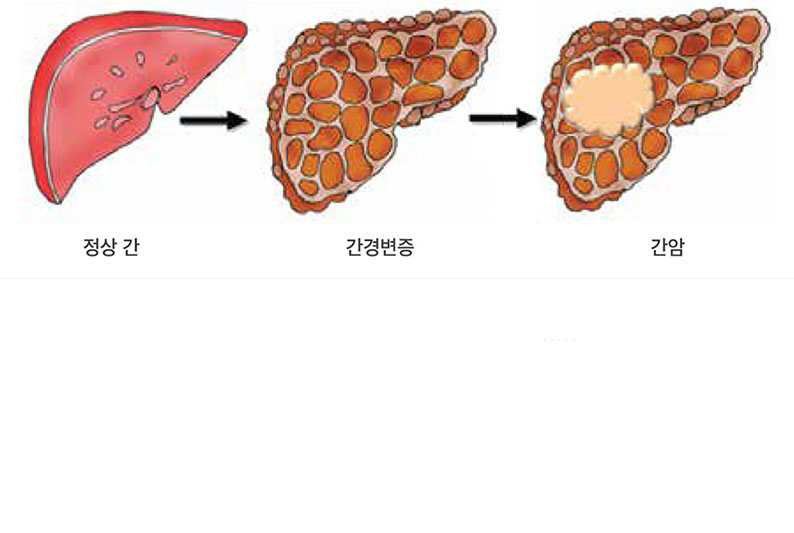

간암의 주원인은 B형과 C형 간염바이러스의 감염과 과도한 음주, 흡연 등 입니다. 최근의 한 통계에 따르면 간암 환자의 72%가 B형 간염바이러스(HBV, hepatitis B virus), 12%가 C형 간염바이러스(HCV, hepatitis C virus)의 영향을 받았으며, 9%가 알코올, 4%가 기타 원인과 연관이 있었습니다. 해마다 간경변증 환자의 1~5%에서 간암이 발생합니다. 간암은 간경변증이 심할수록, 연령이 높을수록 잘 생기고, 남자 환자가 많습니다